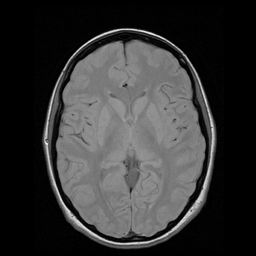

axial1

256 × 256